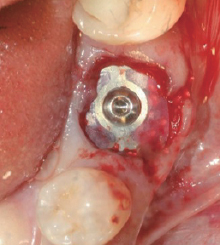

④ BOSS Abutment & Wifi-Mesh

⑤ 3주 치유

⑥ Wifi-Mesh 제거

전, 후 치은 높이보다 1mm 낮게

BOSS Type 1(BOSS Abutment)과 호환 사용 시술 시 고려 사항

Implant 식립 깊이

전후 Bone Level보다 1~2mm 깊게

BOSS Abutment 높이

전후 치은 높이보다 1mm 낮게

BOSS Abutment 선택

치은 높이에 따라 BOSS Abutment 선택